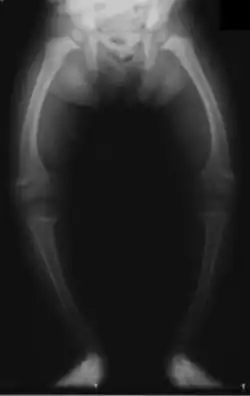

Im zweiten bis dritten Lebensmonat zeigen sich die ersten Symptome in Form von Unruhe, Schreckhaftigkeit, vermehrtem Schwitzen und dadurch ausgelöstem juckendem Hautausschlag (Miliaria). Etwa einen Monat später kommen eine Muskelschwäche mit Froschbauch, Verstopfungsneigung (Obstipation) und erste Knochenerweichungen am Schädel (Kraniotabes) hinzu. Jetzt kann der Calciummangel zusätzlich zu gesteigerter Muskelerregbarkeit (Tetanie) bis hin zu Krämpfen führen. Wiederum etwa einen Monat später entsteht durch Abflachung des Hinterkopfes und Auftreibung der Schädelnähte (Epiphytenbildung) das Bild eines Quadratschädels. Die perlschnurartig aufgereihten Auftreibungen der Knorpel-Knochen-Grenzen an den Wachstumsfugen der Rippen am Brustkorb wird auch Rosenkranz genannt. Auch Hand- und Fußgelenke verbreitern sich durch Auftreibung der Epiphysen zunehmend (Marfan-Zeichen, „doppelte Glieder“). Später zeigen sich ein verzögerter Zahndurchbruch, Defekte im Zahnschmelz, eine verzögerte Mineralisation der Kieferknochen bis hin zum offenen Biss. Weil der Brustkorb ungewöhnlich weich ist, führt der Muskelzug am Zwerchfellansatz zu einer Einziehung, der Harrison-Furche. Zu den weiteren typischen Knochenverformungen gehören Beinverkrümmungen (O-Beine, Genua vara), wobei die langen Röhrenknochen varisch (nach innen) verbogen sind, und die Fehlstellungen weniger im Gelenk selbst liegen. Bei Erwachsenen sind die Wachstumsfugen schon verschlossen und es kommt bei einem Vitamin-D-Mangel lediglich zu einer Osteomalazie ohne die im Kindesalter so typischen Knochenverformungen.

Die Diagnose wird durch die typischen Symptome, die im Röntgenbild sichtbaren Veränderungen an den Knochen sowie durch eine erhöhte Aktivität der Alkalischen Phosphatase im Blut gestellt.[6] Da die Röntgenuntersuchung keine spezifischen Unterscheidungsmerkmale zwischen einer Calciummangel- und einer Phosphatmangel-Rachitis zeigt, muss zwischen diesen Formen durch weitere Laboruntersuchungen unterschieden werden. Hierzu dient eine Bestimmung des Parathormons, das bei calcipenischer Rachitis erhöht und bei der phosphopenischen Form normal ist. Weiterhin wird die Konzentration der einzelnen Vitamin-D-Vorstufen bestimmt um eine klassische Vitamin-D-Mangel-Rachitis (mit erniedrigten 25(OH)Vitamin-D3-, aber niedrig normalen Dihydroxy-Cholecalciferol-Werten) von den Vitamin-D-abhängigen Formen (mit normaler 25(OH)Vitamin-D3- und abnorm niedriger Dihydroxy-Cholecalciferol-Konzentration bei der VDAR I beziehungsweise normaler Vitamin-D3- und exzessiv hoher Dihydroxy-Cholecalciferol-Konzentration bei der VDAR II) abzugrenzen.

Knochenfehlstellungen heilen bei Kindern bei der klassischen Rachitis nach Substitution von Vitamin D meist selbständig aus, bei schweren Verformungen der Beine werden allerdings oberschenkellange Schienen empfohlen (Orthesen). Bei den Phosphatmangel-Formen und bei Jugendlichen sind deutlich häufiger Korrekturosteotomien notwendig, bei denen durch eine Knochenkeilentnahme mit anschließender Osteosynthese der Achsfehler korrigiert wird.